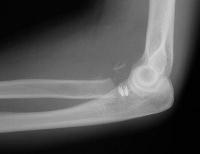

Initial reduction, elsewhere.